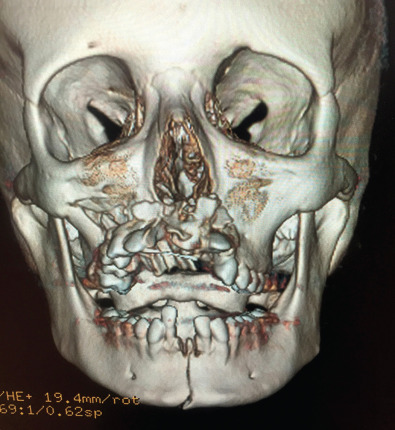

Plain films of the craniofacial skeleton, especially the midface, are of no use in the assessment of facial trauma in the pediatric population. Developing sinuses and tooth buds may obscure already overlapping planes. Computed tomography (CT) scans are necessary in order to accurately diagnose pediatric facial trauma. Fine facial cuts are necessary to adequately define facial fractures, and 3D reconstructions can be extremely useful in planning surgical intervention and teaching trainees. Cone beam CT scans and orthopantomograms (panoramic radiographs or panorex) are also useful to assess for dental injuries.

Facial fractures in children are often less displaced than those of adults and greenstick fractures are common given their more flexible bones with more mobility at suture lines and less bone mineralization. The bone exhibits a higher cancellous-to-cortical bone ratio, and without the development of the air-filled paranasal sinuses which affect the compliance of the craniofacial skeleton. At birth, the maxillary sinus is present but very small, enlarging gradually downward as the permanent dentition erupts, to fill the area previously occupied by the tooth buds. As such, it does not reach its adult size until eruption of the third molars. Ethmoid air cells are also usually present at birth, slowly expand, and are the first sinuses fully developed, which occurs around puberty ( Fig. 2.4.2 ). The sphenoid sinus first appears around age 2 and continues to enlarge until skeletal maturity, with some further septation into adulthood. The frontal sinus first appears at age 5 and continues to expand into late teen years. Increased soft tissue padding, thicker fat pads, and the strong, developing tooth buds within the maxilla and mandible also provide increased resistance to complete fractures ( Fig. 2.4.3 ). While these factors act to provide protection for the pediatric skeleton, a higher impact force per unit area is required for the facial bones to fracture in children compared with their adult counterparts and as such, there may be a higher incidence of associated injuries. The unique nature of the elastic compliant pediatric craniofacial skeleton can result in greenstick fractures and discontinuity between fracture zones ( Fig. 2.4.4 ).

Pediatric midfacial fractures are classified anatomically and will vary according to the age of the patient. The velocity of the injury will give clues to the types of fractures seen. The orbitozygomatic and nasal regions are susceptible to lower velocity trauma than the midface maxillary complex. The degree of displacement and comminution will be used to classify these fractures. Naso-orbito-ethmoid fractures are quite rare in young children due to the flatter nasal dorsum but may be classified according to the degree of comminution of the segments containing the medial canthal ligament (Type I: large fragment; Type II: small fragment; Type III: canthal avulsion). The typical Le Fort fracture classification may be applied but usually does not occur until teen years when the maxillary sinuses have aerated and the teeth erupted. Dentoalveolar fractures are much more common in the pediatric population. Midface fractures in the pediatric age group follow oblique and unpredictable lines extending often into the cranial base and frontal areas. The palatal suture does not fuse until teen years and midline palatal fractures may be more commonly seen in children.